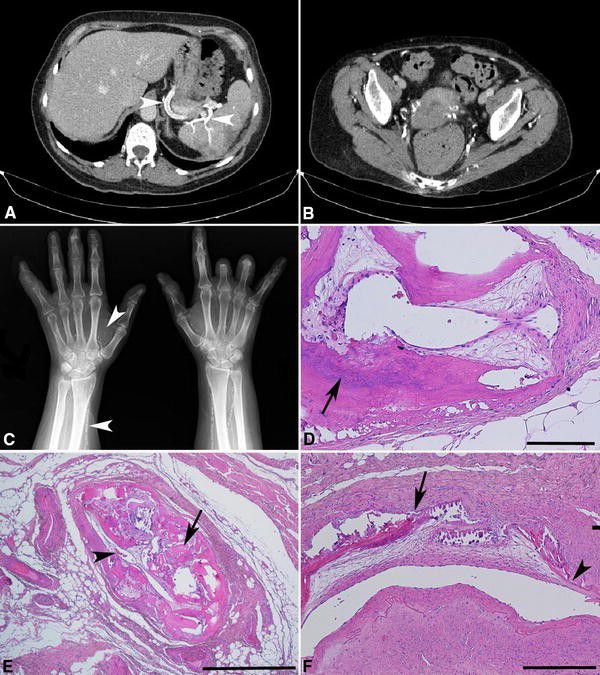

Monckeberg medial calcific sclerosis is a circumferential, diffuse calcifications in the media of small and medium sized arteries. There is no intimal thickening. The cause of Monckeberg medial calcific sclerosis is idiopathic. However, it may be associated with advanced age, chronic kidney disease, and diabetes mellitus. Reference: https://radiopaedia.org/articles/monckeberg-medial-calcific-sclerosis-2 Image via: https://link.springer.com/article/10.1007/s11739-018-1794-1